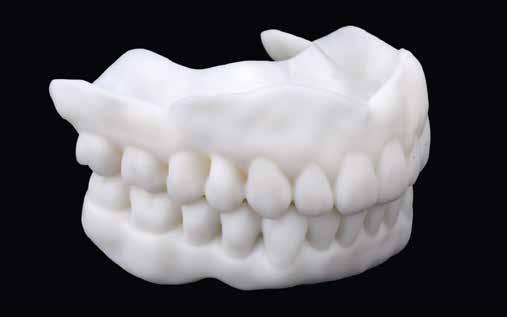

A 75 éves páciens új fogsorokat szeretett volna. Felül nem kielégítő teljes lemezes kivehető fogsora volt, alul pedig szintén nem megfelelő részleges fogsora, néhány devitális, apikális oszteolízist és masszív szekunderkárieszt felmutató mutató maradék frontfogon. Az endodonciai beavatkozást a páciens elutasította. Ehelyett kerámiaimplantátumokra alapozott kezelést kívánt. Az úr általános egészségi állapotában panaszok mutatkoztak. A CMD-index nem volt számottevő. A DVT-vizsgálat (1. kép) alapján megállapítható a 42-es fog decens apikális oszteolízise, számottevő vertikális és horizontális csontveszteség a rágóterületen, valamint az

1. kép: Kiindulási helyzet: az OPG hat devitalizált alsó frontfogat ábrázol, részleges apikális oszteolízissel, szekunderkáriesszel, horizontális csontfelszívódással a rágóterületen.

2. kép: 6 egyrészes SDS kerámiaimplantátum azonnal behelyezve az extrakciót követően.

3. kép: A laborkészítésű formát felhasználva alakították ki az ideiglenest.

4. kép: Kontrollfelvétel: a posztoperatív helyzet az ideiglenessel a hat implantátumon.

FDOK/NICO értelmében HU alapján mért erőteljes csontsűrűség-csökkenés mutatkozik az 18, 17, 13, 23, 27 és 28 fogak régiójában.

Terápia és implantáció

Az operatív beavatkozás előtt a behelyezett fogsorokkal és azok nélkül is beszkennelték az intraorális szituációt, valamint elkészítették a fogsorok digitális másolatát. Ezután óvatosan kihúzták a maradék fogakat, és mindent előkészítettek az azonnali implantációhoz, amelynek során 6 egyrészes SDS kerámiaimplantátumot terveztek behelyezni a meglévő alveolusba a 34-43 közötti területre. Közvetlenül a behelyezést megelőzően a szék mellett még egyszer megtisztították Diener Denta Plas plazmakészülékkel (lásd 49. kép) az implantátumokat, a lehető legteljesebb csírátlanítás – így a páciens csíraterhelésének minimalizálása – érdekében (2. kép) Az alveolus ózonos tisztítását követően behelyezték a hat egyrészes SDS kerámia-implantátumot, A-PRF (saját vérlemezkében gazdag – a ford.) membránokkal megsegítve. A laborkészítésű előre mintázott elemek alapján azonnali ide-

iglenes került az implantátumokra (3. kép), majd röntgennel újólag ellenőrizték a létrejött helyzetet (4. kép)